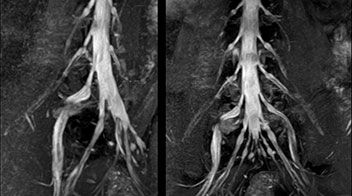

“NerveVIEW can clearly show nerve courses and presence of nerve compression. However, when multiple abnormalities are seen, it can still be hard to determine which nerve is causing the symptoms,” says Dr. Yabuki. “In our experience so far, we see abnormal findings on NerveVIEW in about 70% of elderly patients. As the pain is usually caused by only one nerve, we thus need to find the exact corresponding nerve.” “With a nerve root block, the patient's pain is improved by infiltration of local anesthesia directly around the nerve root considered to be responsible. Knowing such nerve root block findings prior to image interpretation, helps to easily recognize abnormal findings on NerveVIEW as well. In other words, without a priori knowledge, based on symptoms and/or nerve root block findings, we must be aware of the possibility of overdiagnosis.”

The addition of the nerve-selective NerveVIEW sequence to its spine MRI protocol has given NFMC competitive advantages, according to Tanji. “Since we started including NerveVIEW routinely, the demand for lumbar spine MRI examinations has increased, especially for pre-surgical planning purposes and for patients with chronic lower extremity symptoms,” he says. “Moreover, because no other hospitals in our region are doing nerve plexus imaging yet, we often receive referrals for MR neurography studies from other hospitals even if they have an MRI scanner. Some requests come from as far as 100 km away. NerveVIEW definitely provides us a competitive advantage.” “Based on our experience, we can certainly recommend NerveVIEW to other centers,” Dr. Yabuki adds. “The sequence opens up many possibilities to facilitate the diagnosis of lower extremity pain and to inform our decision-making regarding therapy and surgery.”